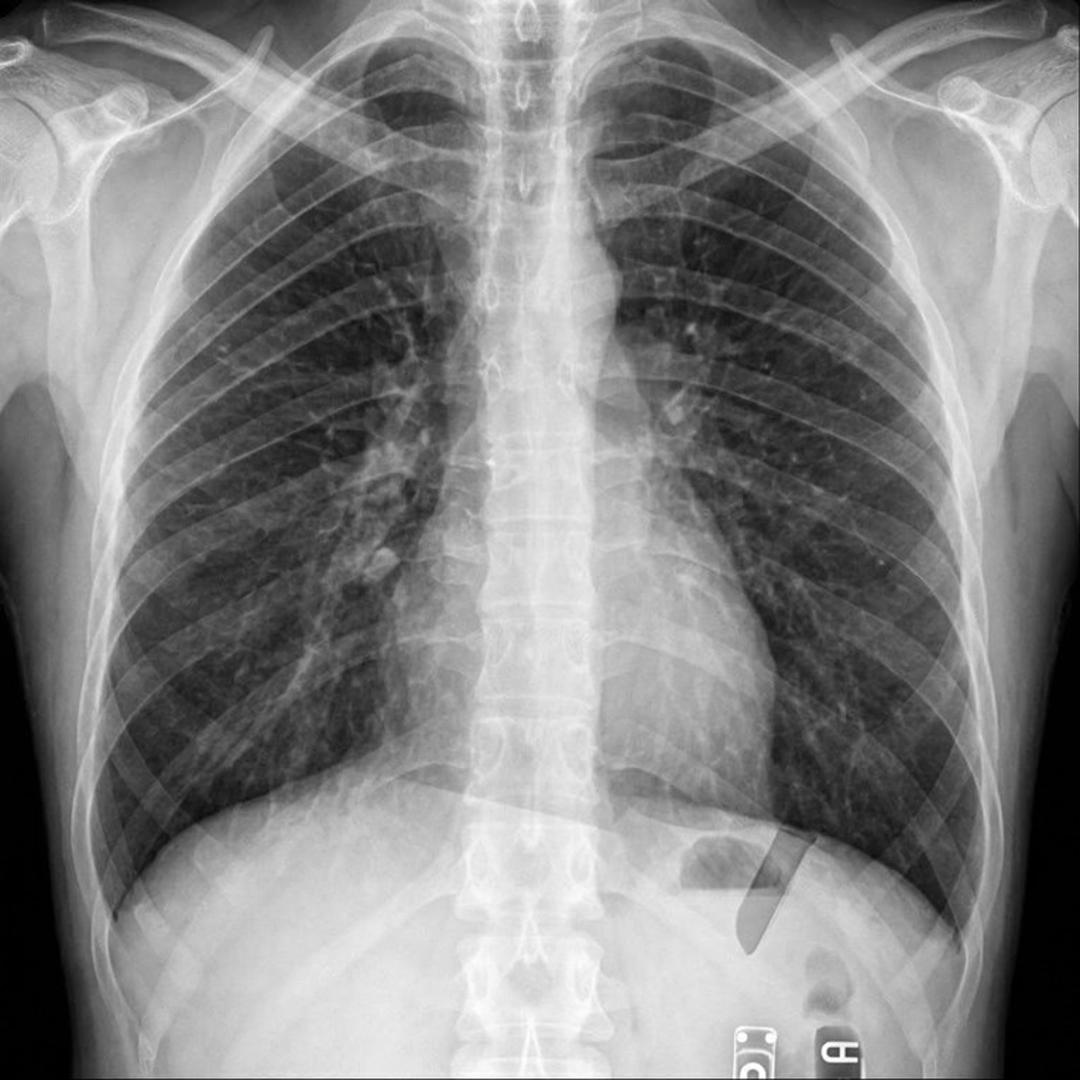

Rendgenska snimka prsnog koša otkrila je bizaran uzrok njegovih tegoba - jedan od izvađenih umnjaka završio mu je u plućima.

Snimka je potvrdila sumnju - umnjak mu je doista završio u plućima. Liječnici su mu objasnili da pacijent u takvoj situaciji obično zakašlje ili proguta zub, no kako je Artur bio pod sedacijom, taj refleks nije radio.

Zub su mu potom izvadili bronhoskopijom, postupkom u kojem liječnici malom kamerom ulaze u dišne putove i pluća kako bi pronašli i uklonili strano tijelo.